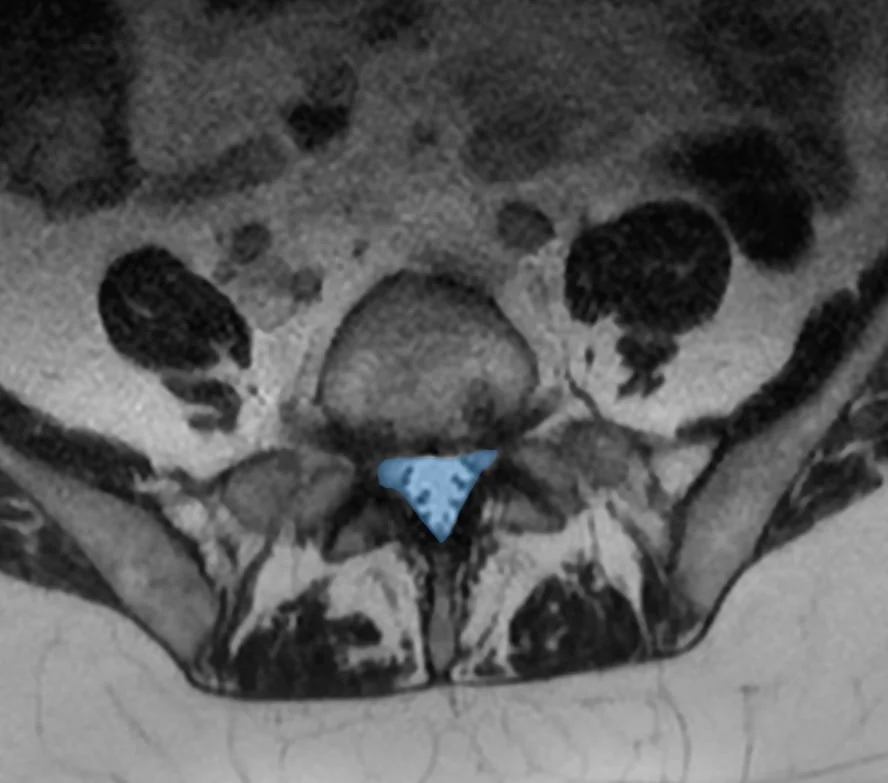

À droite : canal lombaire étroit (en bleu) où les racines nerveuses sont comprimées.